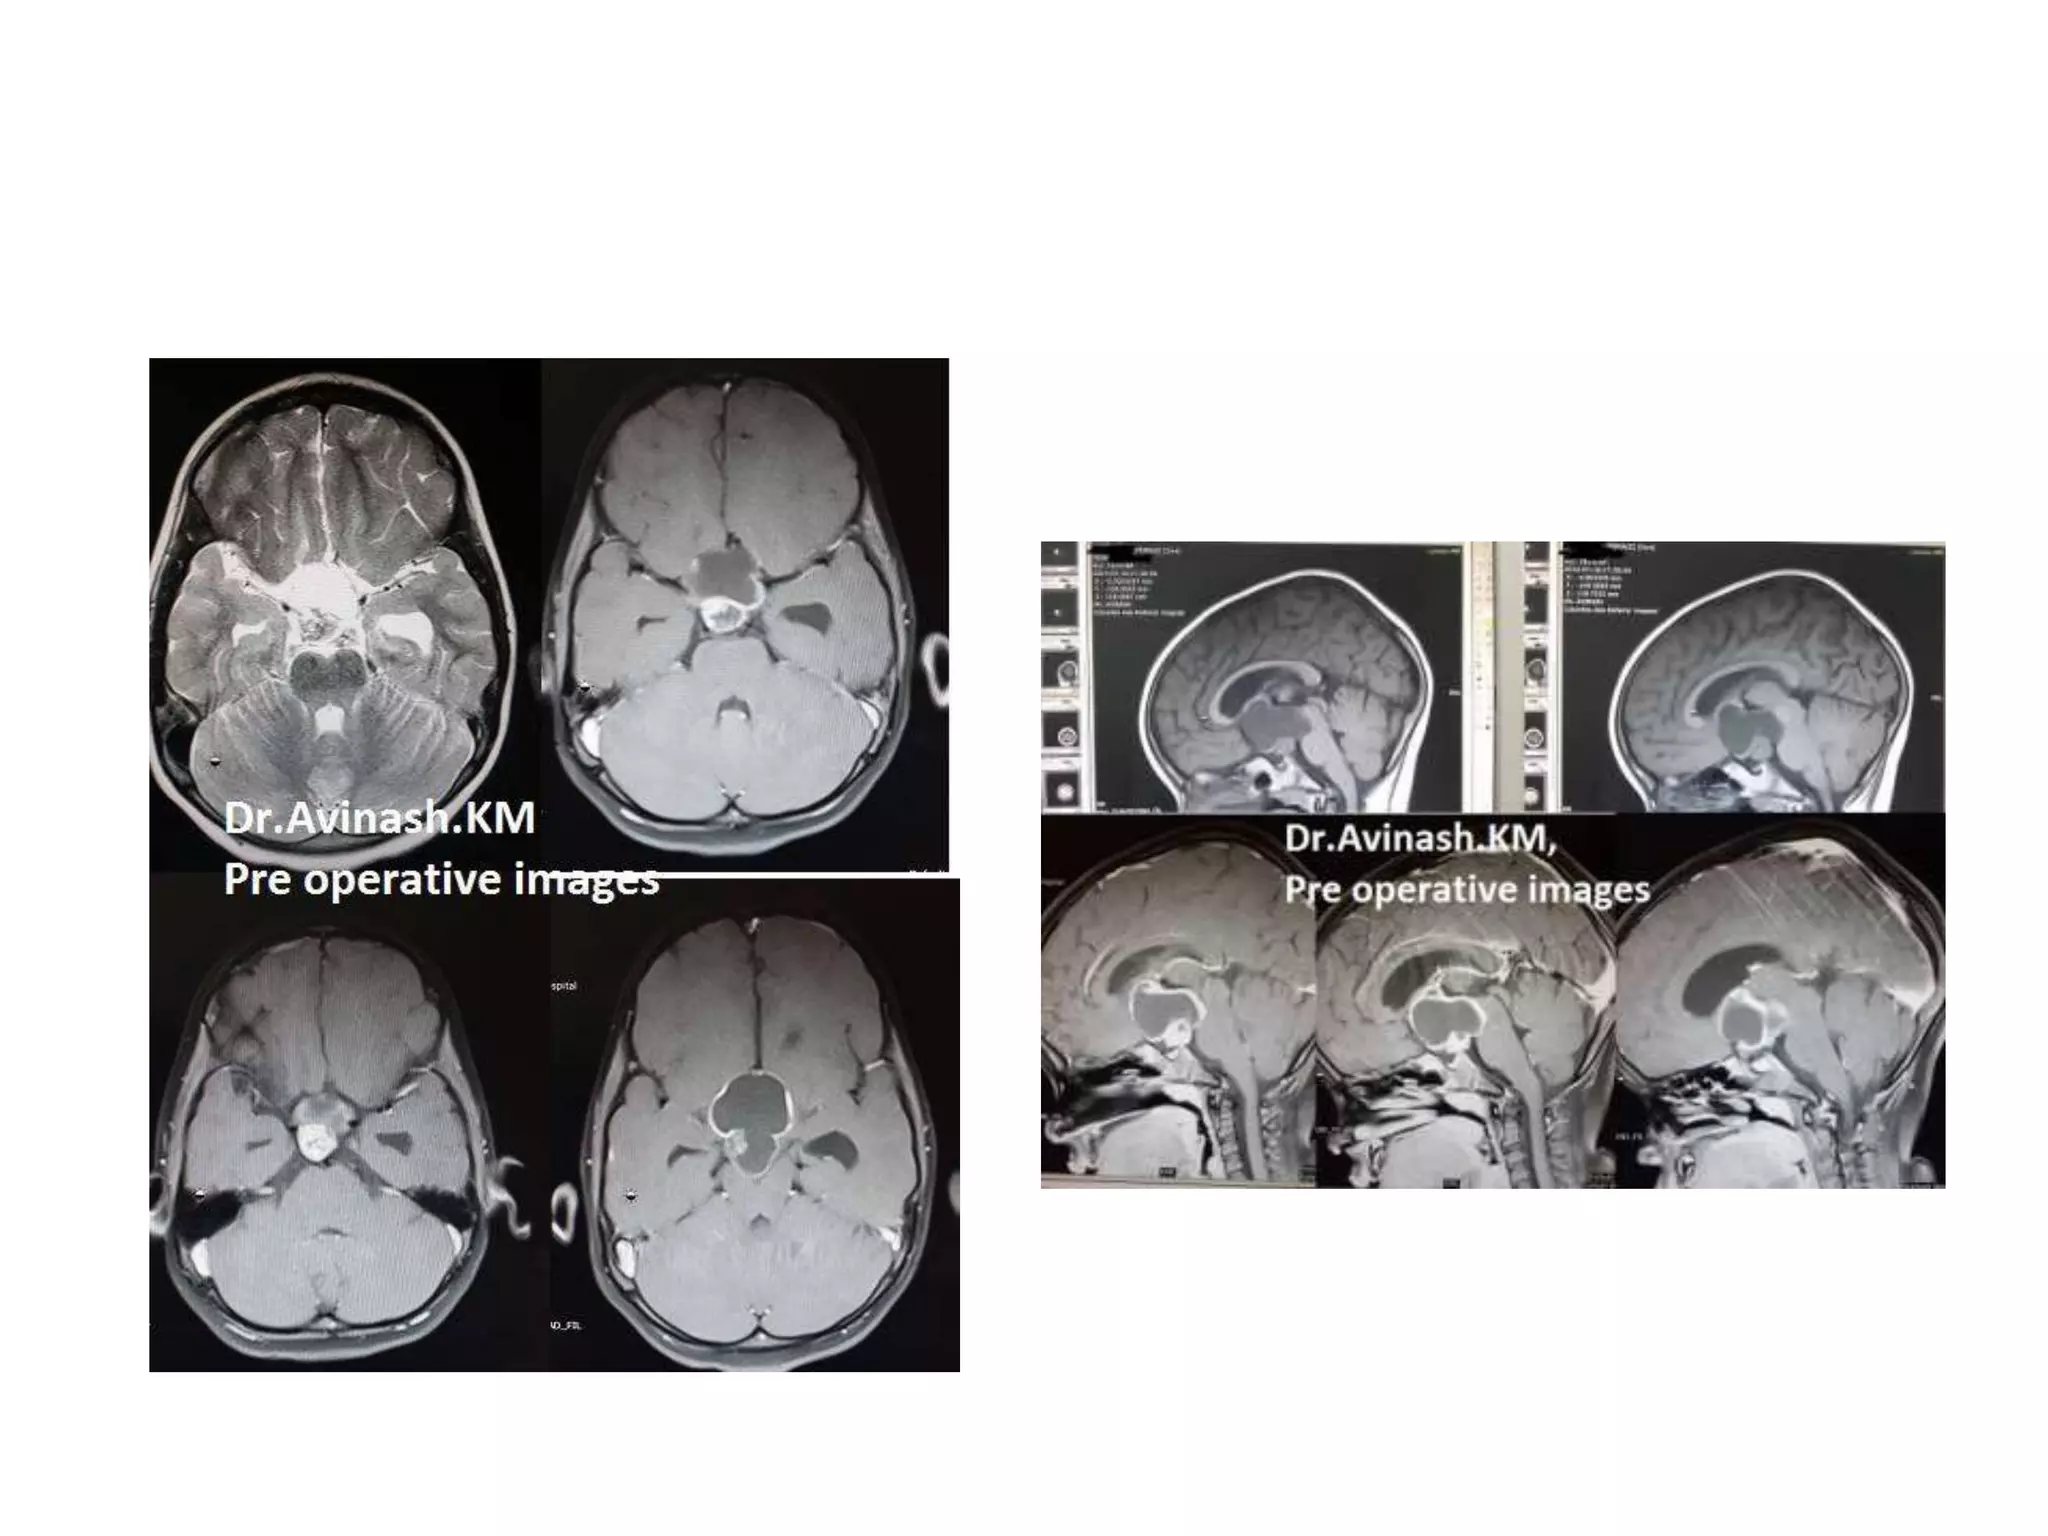

Craniopharyngioma

CRANIOPHARYNGIOMAS-Removal corridors.

FIGURE 4. The capsule of the cystic craniopharyngioma was firmly attached to the left

craniopharyngioma from proximal stalk is recognizable A. Complete removal of the capsule was

possible, but produced subpial blood injection over the left hypothalamic surface B. MRI scan

revealed a small ischemic injury in the left hypothalamus C. This patient had transient sleep

disorder, moderate hyperphagia and memory problems (see also a supplemented video

material 1).

FIGURE 2. In this cystic craniopharyngioma (Patient 5), the stalk was centrally

infiltrated close to the pituitary and could not be preserved A. The incipient third

ventricle entrance is seen from intracavitary view. The slit into the third ventricle is

still covered with tumour capsule B. Complete removal of the capsule opened the

third ventricle C. Petehiae in the hypothalamus bilaterally resulted from apparently

gentle traction and blunt dissection of the capsule away from the hypothalamus

D. Psychoorganic change, disorientation and memory deficits were noticed in less

than a week after surgery, the transient sleep disorder become apparent in the

second week postoperatively (see also a supplemented video material 2).

FIGURE 3. Large craniopharyngioma (Patient 3) produced unilateral hydrocephalus

by obstructing the right formen of Monro A. The dome was filled with soft

cholesterine cristals B, which were easily removed. Lower limbus of the right foramen

of Monro is seen through the empty third ventricle D. Despite bilateral preservation

of anteromedial hypothalamus C and stalk preservation E, the patient developed

panhypopituitarism and diabetes insipidus with long lasting psychoorganic change